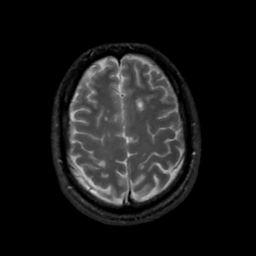

MR Study #1, February 10, 1991 -- Slice #39

[Home][Help][Clinical][Tour 1][Tour 2] Slice 39